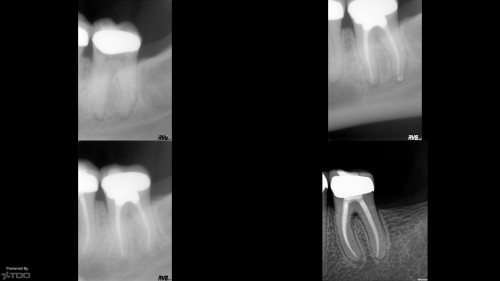

#3 Pulpitis. Er. RCT

#3 Er. RCT. Pulpitis probably following a recent amalgam close to the distal pulp horn. […]